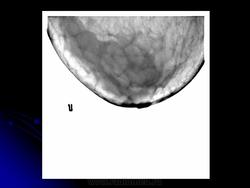

Со старением железистая ткань постепенно исчезает: прозрачность жировой ткани становится преобладающей с несколькими каркасами, связанными с опорными волокнистыми структурами.

Жирная (не плотная) грудь

Умеренно плотная грудь

Плотная грудь

Маммограммы представляют собой изображения структур, проецируемых на плоскость: плотная грудная маммограмма, следовательно, состоит из многих других структур, которые необходимо проанализировать, чем более жирная, пустая грудь. По этой причине диагностировать рак молочной железы труднее для моложе, чем для пожилых женщин.

Нажмите на миниатюрные картинки, чтобы получить увеличенный размер.